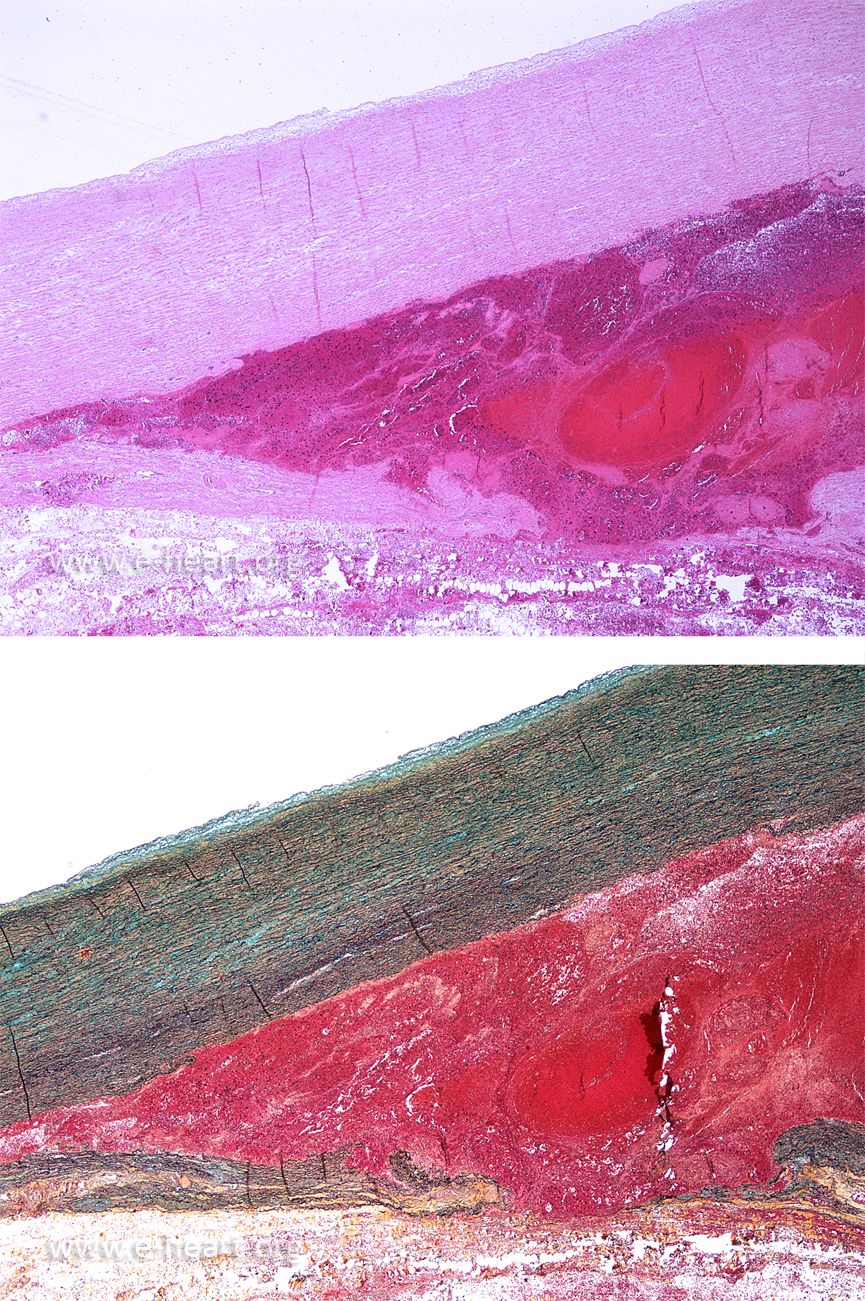

The image on the left shows an acute aortic dissection. The media of the aorta shows a dissection plane filled with blood which is extravasating into the adventitia.

The image on the right shows a chronic dissection plane. Note that the dissection plane is filled with connective tissue instead of blood. This connective tissue represents the formation of "neointima" in the false lumen of the dissection. The curled appearance of the intimal tear is due to retraction by the organized neointima.